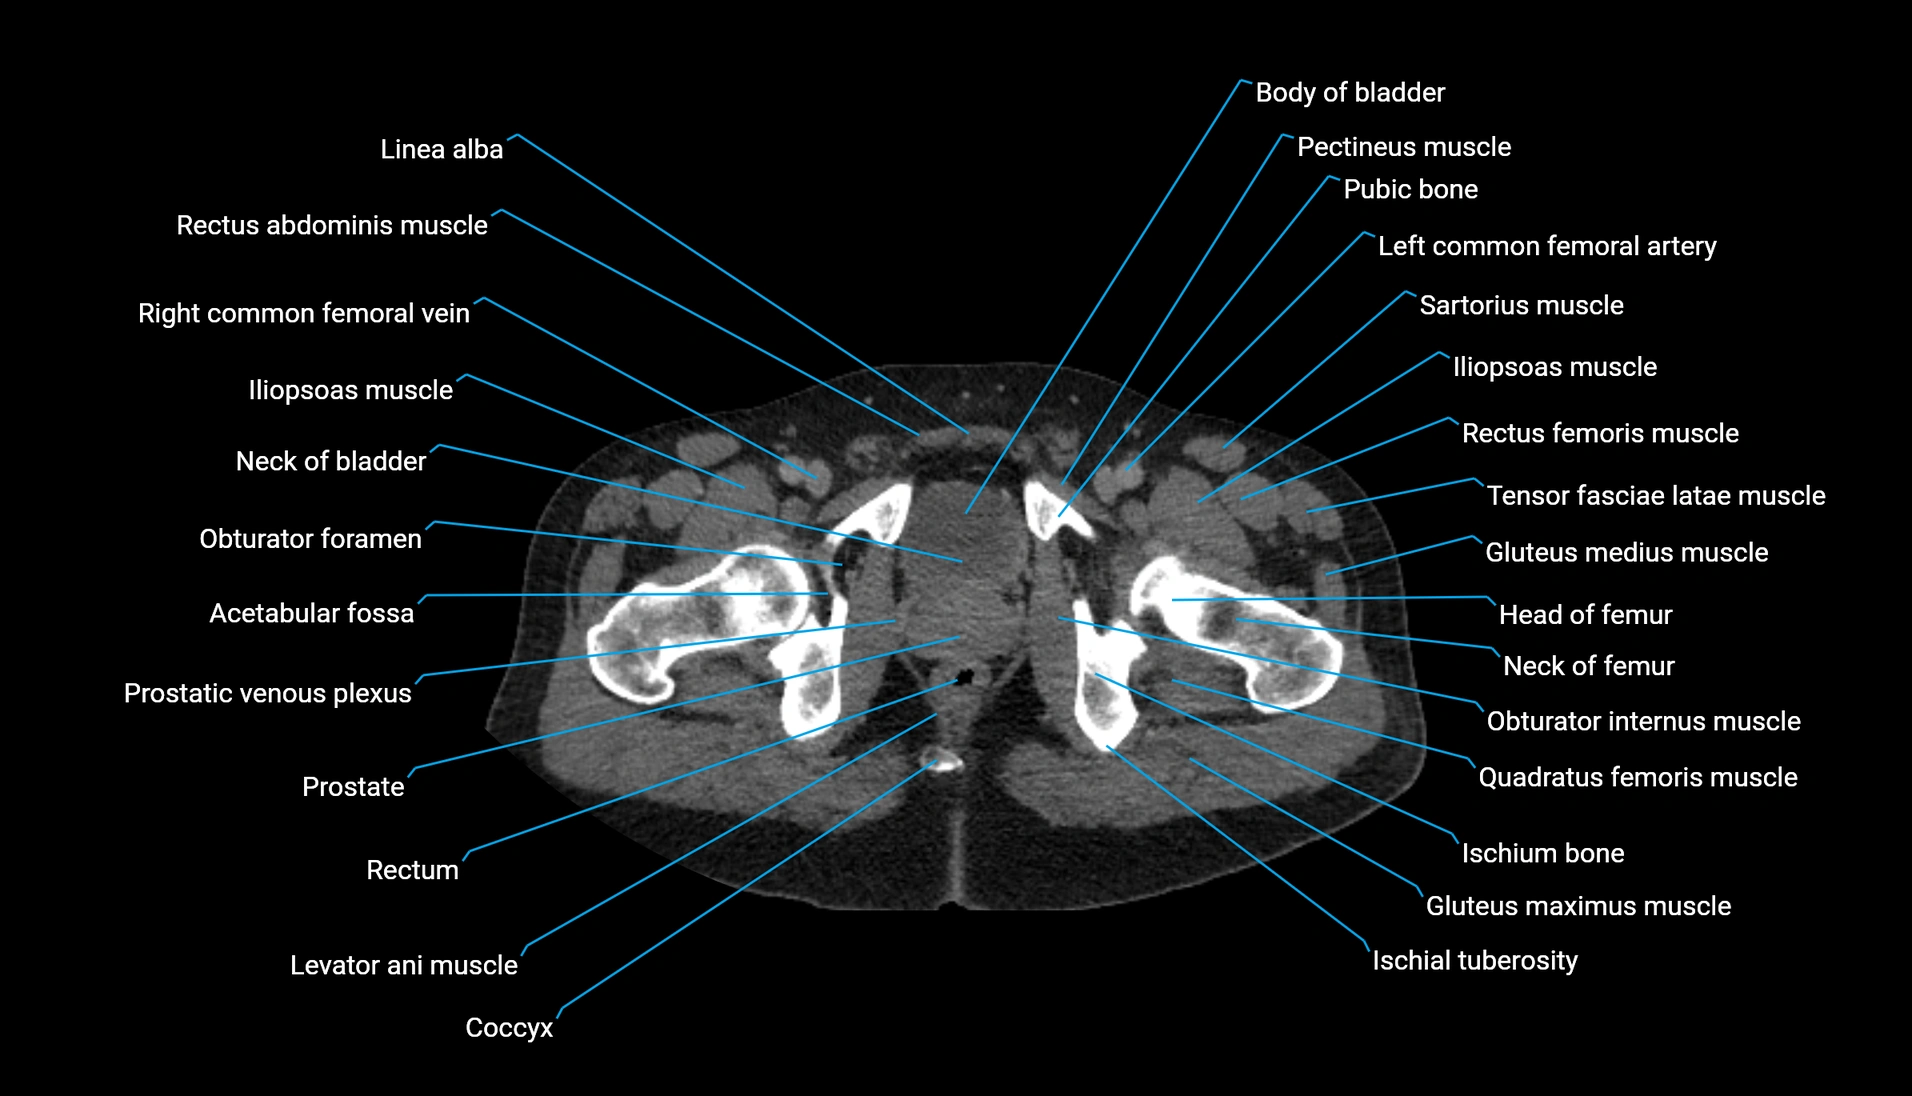

The acetabular margin, also called the acetabular rim, is the bony edge of the acetabulum, the cup-shaped cavity on the lateral aspect of the pelvis that articulates with the head of the femur to form the hip joint. The acetabular margin consists of the superior, anterior, and posterior borders of the acetabulum and is interrupted inferiorly by the acetabular notch.

The rim provides attachment for the acetabular labrum, a fibrocartilaginous structure that deepens the acetabulum, increasing hip joint stability. The transverse acetabular ligament bridges the acetabular notch, completing the bony ring. Superiorly, the margin bears the greatest load during standing and gait, making it the most common site of degenerative changes.

The acetabular margin is clinically significant in femoroacetabular impingement (FAI), acetabular fractures, hip dysplasia, and osteoarthritis. Its morphology (depth, coverage, and orientation) is a key factor in hip biomechanics and surgical planning, especially in arthroscopy and hip preservation surgery.

CT Appearance

Non-contrast CT:

-

Demonstrates cortical bone of acetabular rim in excellent detail

Detects fractures, dysplasia, retroversion, or bony overcoverage (pincer impingement)

3D reconstructions used in preoperative hip surgery planning

CT VRT 3D image

CT image